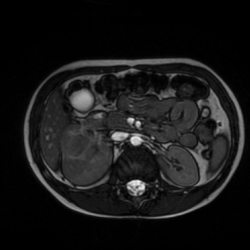

МРТ без контраста , несколько снимков прикрепляю.